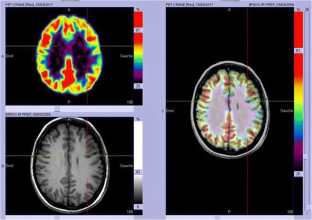

To assess the localizing value of 18F-FDG PET in patients operated on for drug-resistant epilepsy due to focal cortical dysplasia type 2 (FCD2).

We analysed 18F-FDG PET scans from 103 consecutive patients (52 males, 7–65 years old) with histologically proven FCD2. PET and MRI data were first reviewed by visual analysis blinded to clinical information and FCD2 location. The additional value of electroclinical data and PET/MRI coregistration was assessed by comparison with pathological results and surgical outcomes.

Visual analysis of PET scans showed focal or regional hypometabolism corresponding to the FCD2 in 45 patients (44%), but the findings were doubtful or misleading in 37 patients and negative in 21. When considering electroclinical data, positive localization was obtained in 73 patients, and this increased to 85 (83%) after coregistration of PET and MRI data. Under the same conditions, MRI was positive in 61 patients (59%), doubtful in 15 and negative in 27. The additional value of PET was predominant in patients negative or doubtful on MRI, localizing the FCD2 in 35 patients (83%). Interobserver agreement correlated with the grade of hypometabolism: it was good in patients with mild to severe hypometabolism (82–95%), but moderate in those with subtle/doubtful hypometabolism (45%). The main factors influencing positive PET localization were the grade of hypometabolism and the size of the FCD2 (P < 0.0001). Misleading location (nine patients) was associated with a small FCD2 in the mesial frontal and central regions. Following limited cortical resection mainly located in extratemporal areas (mean follow-up 5.6 years), a seizure-free outcome was achieved in 94% of patients, including Engel’s class IA in 72%.

In this series, 18F-FDG PET contributed to the localization of FCD2 in 83% of patients. This high localizing value was obtained by integration of electroclinical data and PET/MRI coregistration. This approach may help improve the surgical outcome in extratemporal epilepsy, even in patients negative on MRI.